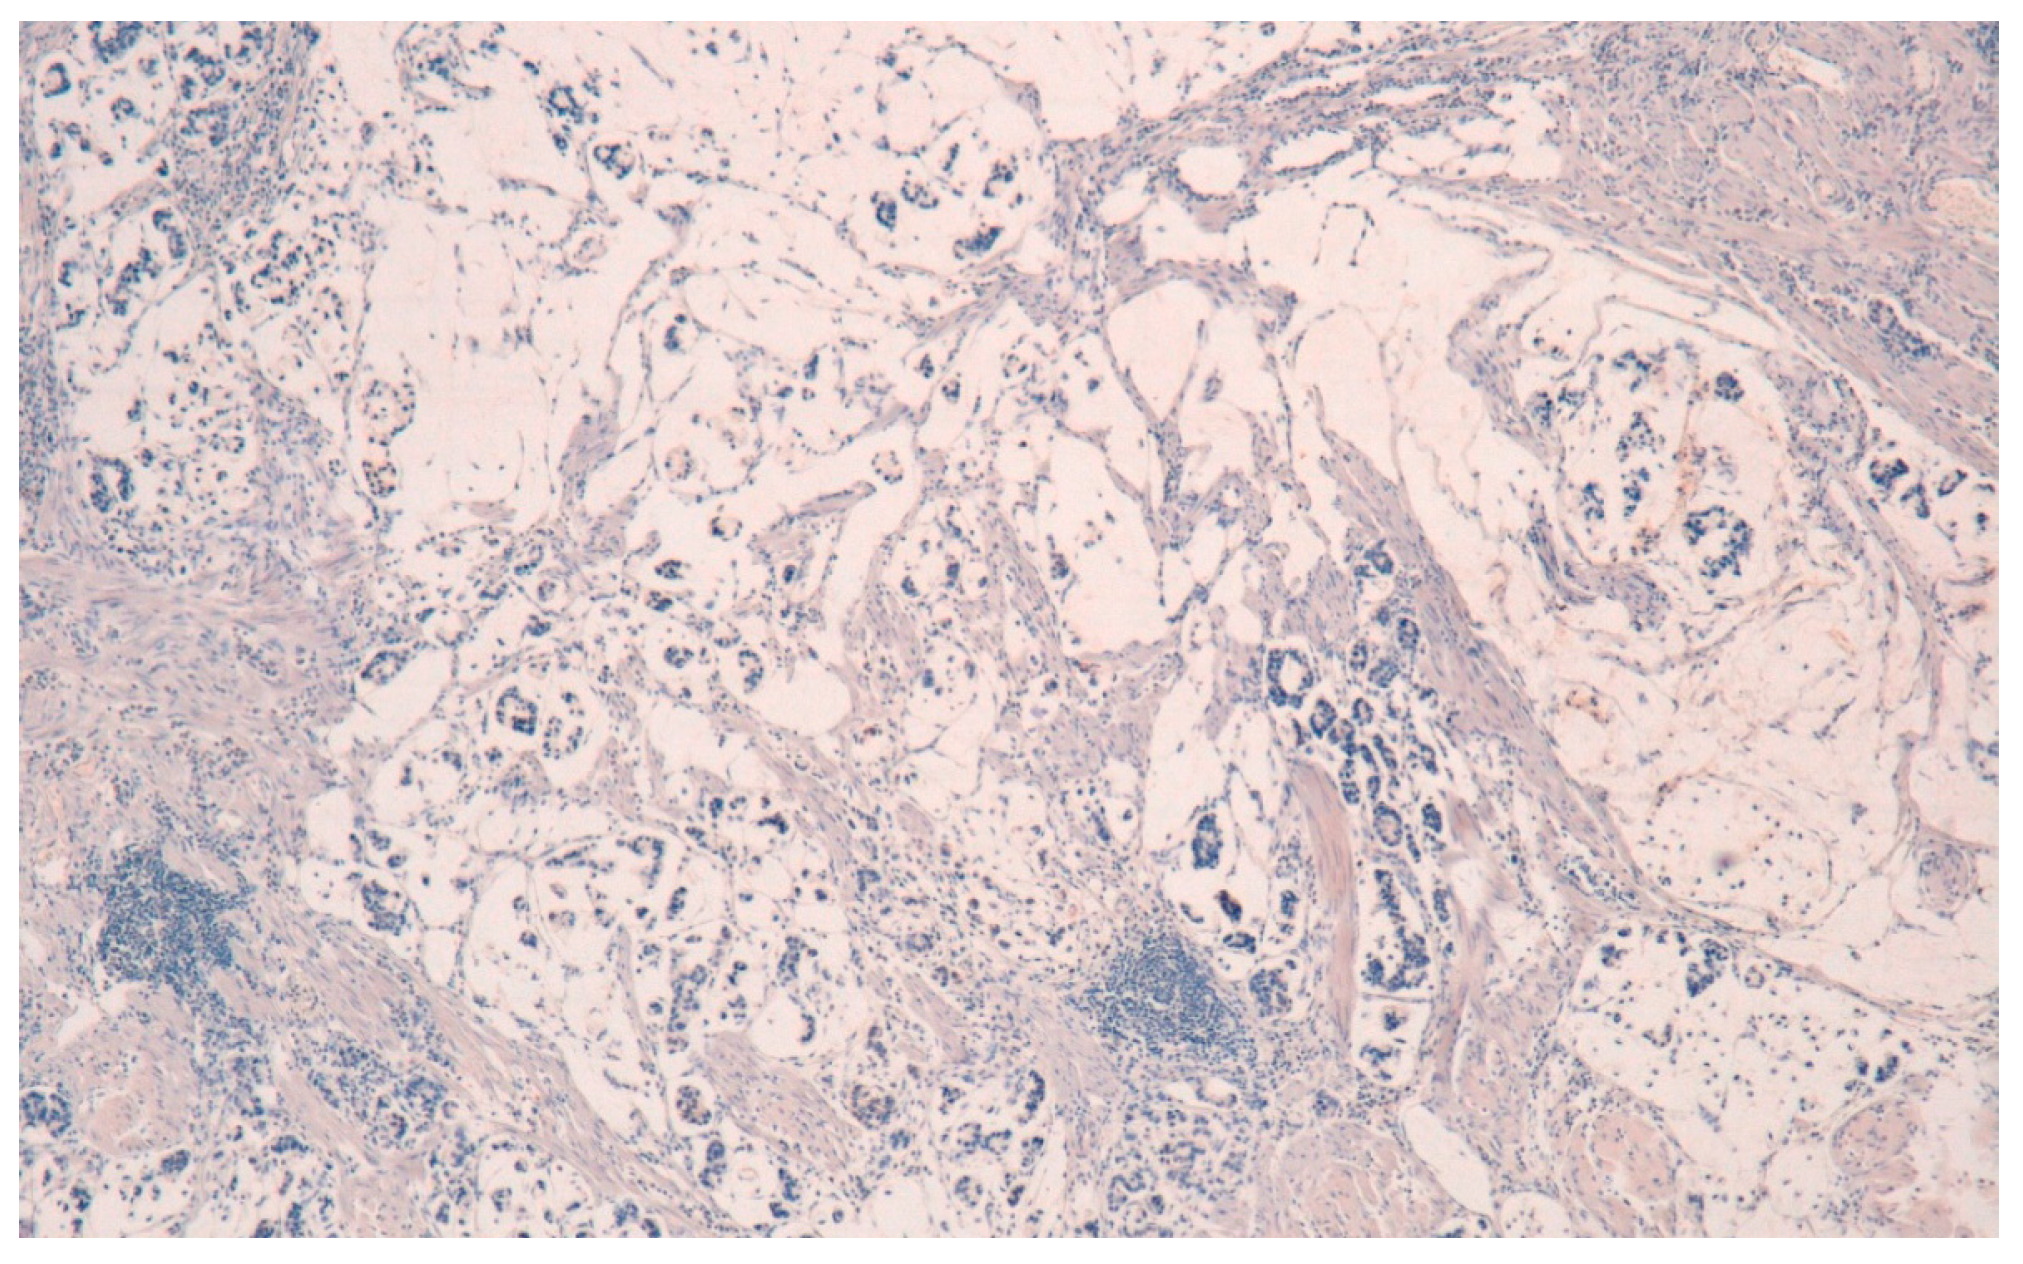

6. Early Gastric Cancer

- Tsukashita, S.; Kushima, R.; Bamba, M.; Sugihara, H.; Hattori, T. MUC gene expression and histogenesis of adenocarcinoma of the stomach. Int. J. Cancer 2001, 94, 166–170. [Google Scholar] [CrossRef] [PubMed]

- Saito, A.; Shimoda, T.; Nakanishi, Y.; Ochiai, A.; Toda, G. Histologic heterogeneity and mucin phenotypic expression in early gastric cancer. Pathol. Int. 2001, 51, 165–171. [Google Scholar] [CrossRef] [PubMed]

- Egashira, Y.; Shimoda, T.; Ikegami, M. Mucin histochemical analysis of minute gastric differentiated adenocarcinoma. Pathol. Int. 1999, 49, 55–61. [Google Scholar] [CrossRef] [PubMed]